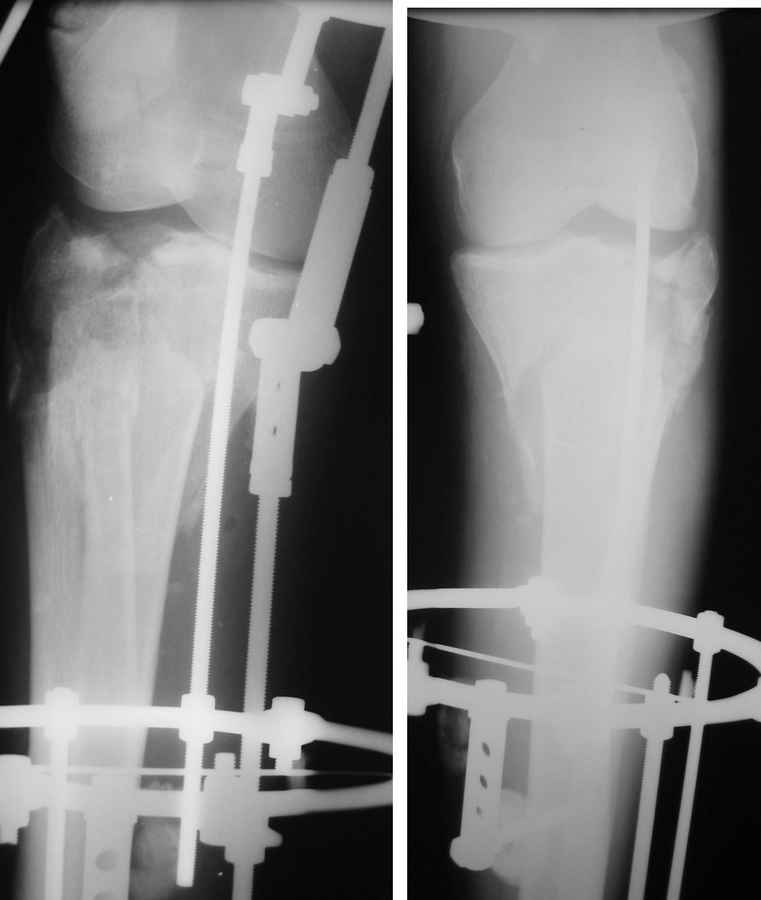

Саша, а в чем конкретно неясность? Надо полагать, вопрос не про общие принципы лечения переломов типа Schatzker VI или C3 по классификации AO, которые можно найти в любом руководстве?

Состояние мягких тканей оказалось принципиальным в разработке плана операции.

Очаг некроза 4 на 5 см по передней поверхности голени не оставил никакого варианта кроме внешнего остеосинтеза.

Но решили делать в 2 этапа. Первый - восстановить ось и дать костной крошке в проксимальном отделе консолидироваться.

Второй - собственно артродез.

Но по результатам первого этапа думаем дать пациенту попользоваться ногой. А там посмотрим.

Почему??? Есть сухой некроз по передней поверхности, но вне зоны возможных хирургических доступов...-

Для первого этапа достаточно. Через 5-10 дней мы бы приступили к следующему этапу. А именно, фиксация из ограниченного заднемедиального доступа 1\3 трубчатой или рекон пластиной медиального фрагмента, и остеосинтез наружного мыщелка из второго тоже ограниченного латерального доступа без артротомии, под контролем ЭОПа..... Сухой некроз в данном случае не являлся бы серьезной помехой для внутренней фиксации (во всяком случае, судя по имеющимся фото)

Я думаю, это не повод сразу думать об артродезе... Конечно уже прошло много времени. Но до месяца у нас есть опыт вполне удачных реконструкций и "переделок"...

P.S. безусловно, с двумя пластинами LCP, каннюлироваными винтами, хроносом все это дорого... Но того же анатомического и функционального результата можно достичь, используя вместо пластин аппарат Илизарова, и разрезы для репозиции тогда нудны совсем маленькие .